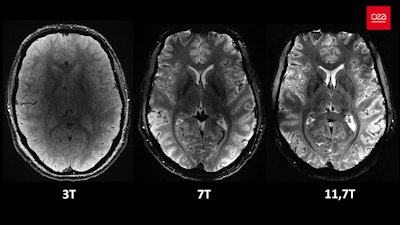

Axial view of the human brain at the same resolution (0.2 mm in-plane resolution and 1 mm slice thickness), with an identical acquisition time of around four minutes but at different magnetic field strengths. At 3 tesla and at 7 tesla (only three such machines in France and around 100 worldwide), the precision and sharpness are lower. At 3 tesla, a "grainy" cloud prevents the anatomical structures of the brain from being clearly delineated. At 7 tesla, when zooming, the level of detail at this resolution is reduced. At 11.7 tesla, the scan provides more signals and greater contrasts between biological tissues, which allows more detailed exploration of the brain. All images courtesy of CEA.